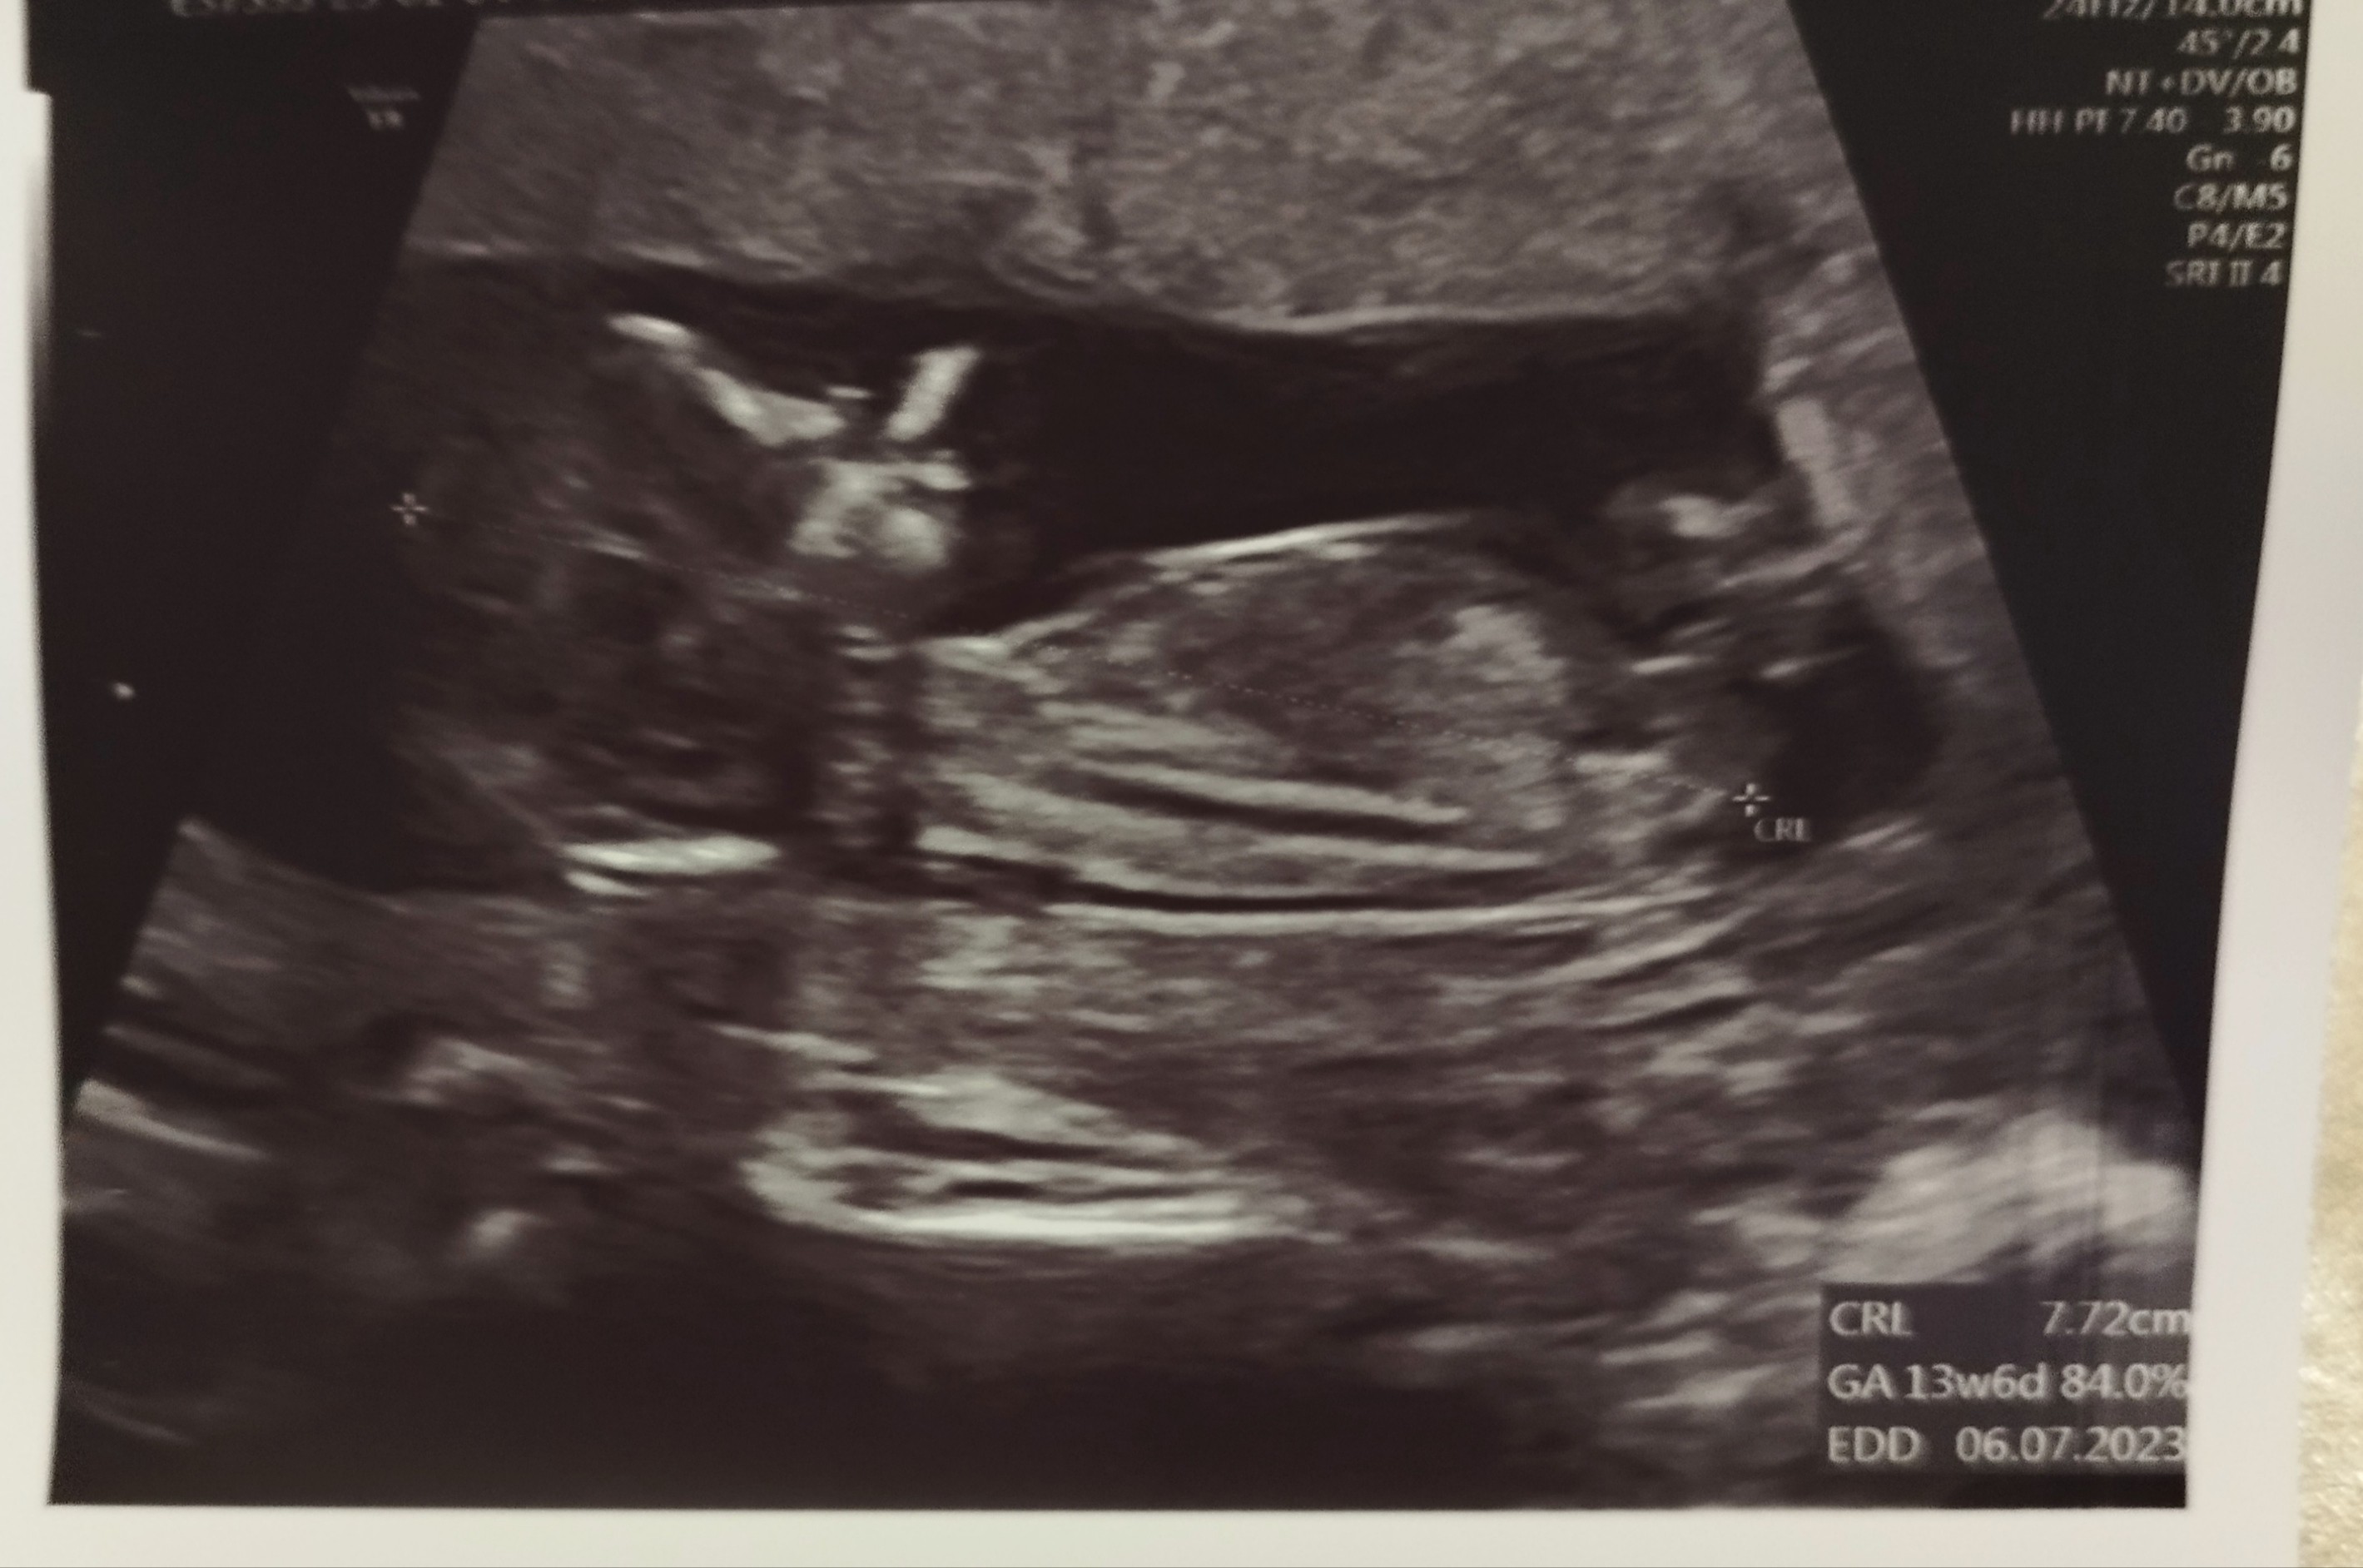

Gratuluję wszystkim wizyt, dużo dzisiaj produkujecie, ja dalej w emocjach więc nie dam rady nadrobić ale wrzucam zdjęcie malucha z dzisiaj. Dalej w szoku że dziewczynka 🙆

Załączniki

• IMG_20230104_191628.jpg

IMG_20230104_191628.jpg

572,5 KB · Wyświetleń: 105